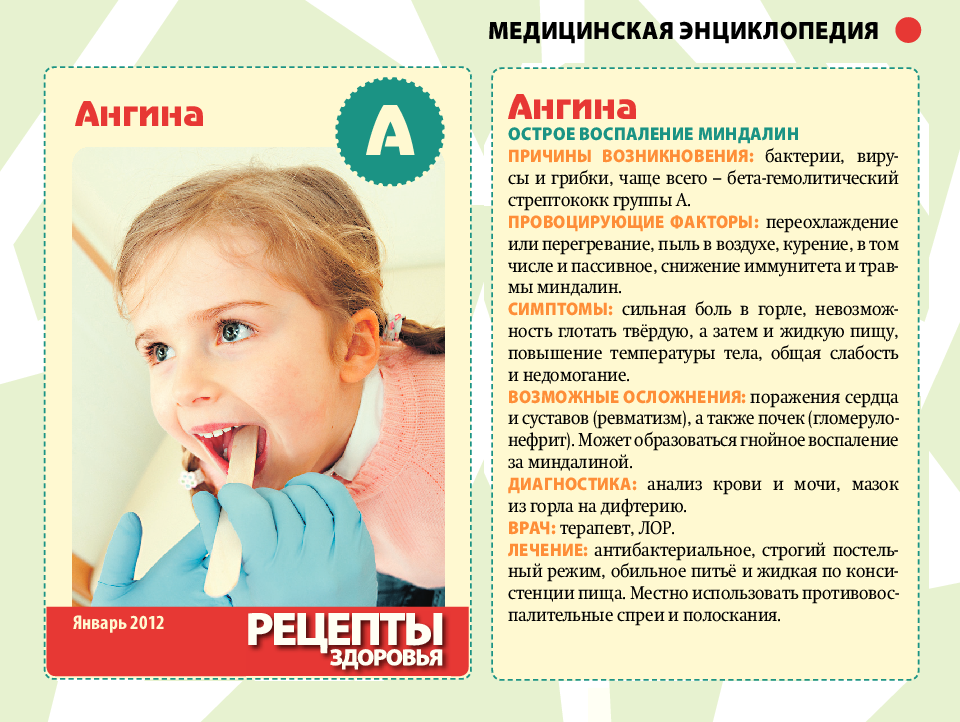

Причины возникновения заболевания

Виновниками гнойной ангины у детей наиболее часто бывают патогенные бактерии: стафилококки, пневмококки, диплококки, стрептококки и прочие. Вся эта микрофлора всегда присутствует в верхних дыхательных путях человека и, если в норме, не опасна для здоровья.

Болезнь возникает в том случае, когда повышается активность микроорганизмов, спровоцированная слабым иммунитетом, а также некоторыми вирусами, такими как аденовирус и грипп. Гнойная ангина чаще всего вызывается микробами, которые живут не только на слизистой оболочке горла, но и на миндалинах, вследствие чего после операции по удалению миндалин ангина практически невозможна.

Помимо этого есть ряд факторов, наличие которых способно повысить вероятность возникновения у детей гнойной ангины. К ним относятся загрязненность воздуха, сырое помещение, переохлаждение, различные виды интоксикации, неожиданные изменения климата, длительное воздействие солнечного излучения, неблагоприятные условия жизни, вредное питание, переутомление.

Симптомы лакунарной ангины

Инкубационный период лакунарной ангины составляет от одного до трех дней. К первым симптомам заболевания относят резкое повышение температуры и болезненные ощущения в горле. Увеличиваться показатели могут до сорока градусов при развитии гнойных процессов. У взрослых температура не повышается выше 37,5 градусов. К другим симптомам принято относить следующие.

- Лихорадочное состояние.

- Озноб.

- Болевое чувство в сердце.

- Ломоту в суставных и мышечных тканях.

- Болезненное ощущение в голове.

- Обильное слюноотделение.

- Ощущение присутствия кома в горле.

- Тошноту и рвоту.

- Увеличение лимфатических узлов в области челюсти и шеи. При пальпировании наблюдается болезненность.

- Общую слабость и повышенную утомляемость.

- Потерю аппетита.

- Бессонницу.

- Проявление гнойных лакун и налета желтоватого цвета. При лакунарной ангине возникает быстрое нарастание симптомов. При своевременном лечении они также мгновенно угасают. Лакунарный тонзиллит в детском возрасте проявляется достаточно тяжело. В некоторых ситуациях возникает судорожное состояние и удушье. Если знать, как лечить лакунарную ангину в домашних условиях, то признаки исчезнут к третьему-четвертому дню. В общем заболевание длится до десяти дней.

Чем лечить ангину у детей

Нужно чётко следовать всем рекомендация лечащего педиатра для скорейшего выздоровления малыша. Эффективное лечение ангины подразумевает обильный приём жидкости, жаропонижающих, антибиотиков, эубиотиков, антигистаминных средств, полоскания горла и витаминотерапии.

Нужно чётко следовать всем рекомендация лечащего педиатра для скорейшего выздоровления малыша. Эффективное лечение ангины подразумевает обильный приём жидкости, жаропонижающих, антибиотиков, эубиотиков, антигистаминных средств, полоскания горла и витаминотерапии.

Важно! Гнойная ангина не допускает любые разогревающие процедуры, такие как компрессы, разогревающие мази и крема в шейной области. Один из способов лечения ангины — это полоскание горла для детей старшего возраста и обработка аэрозолями и спреями маленьких детей

Но полоскание горла это только 1 из вспомогательных способов, т. к. основное лечение заключается в приёме антибактериальных средств

Один из способов лечения ангины — это полоскание горла для детей старшего возраста и обработка аэрозолями и спреями маленьких детей. Но полоскание горла это только 1 из вспомогательных способов, т. к. основное лечение заключается в приёме антибактериальных средств.